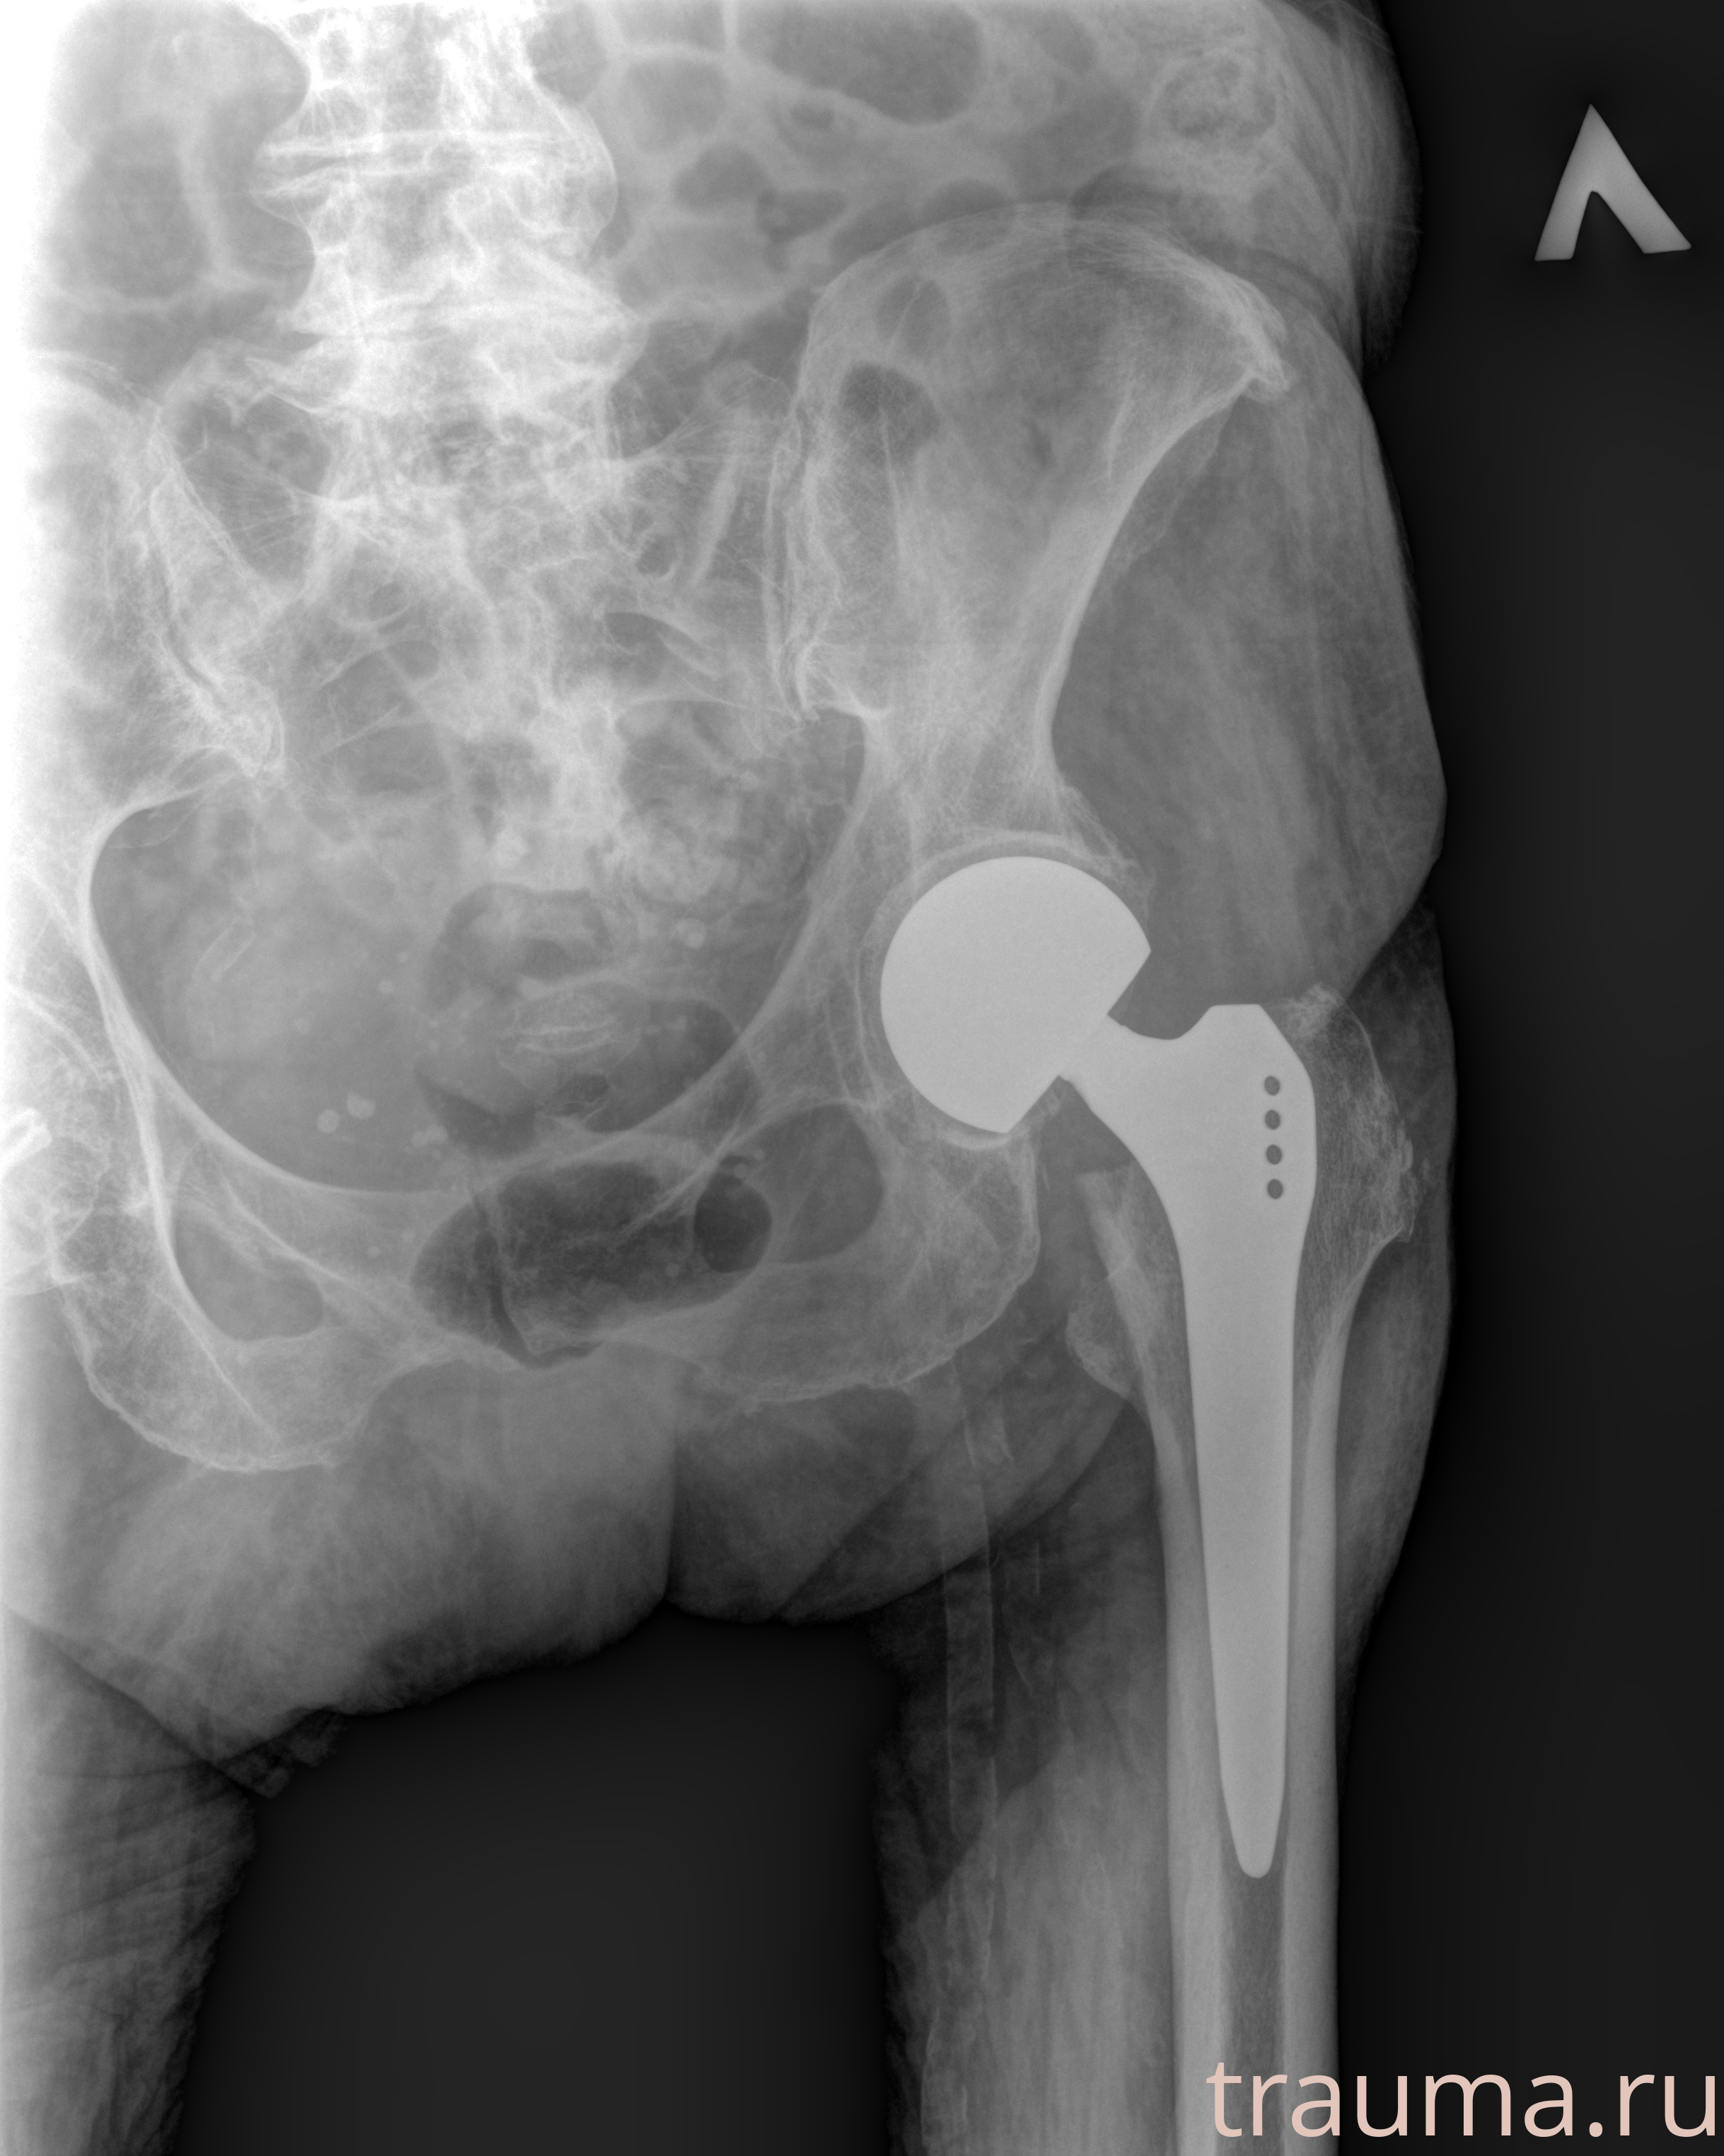

Рентгенограммы

Рентген на дому: по вашему адресу приезжает врач-рентгенолог, травматолог-ортопед с мобильным рентгеновским аппаратом, проводит диагностику травмы или заболевания, делает необходимые рентгенограммы, дает рекомендации по дальнейшему лечению. Получить качественные снимки в домашних условиях возможно благодаря уникальной методике, разработанной МосРентген Центром для института  Склифосовского

при переломе шейки бедра и пневмонии от компании МосРентген Центр - партнера Института имени Склифосовского